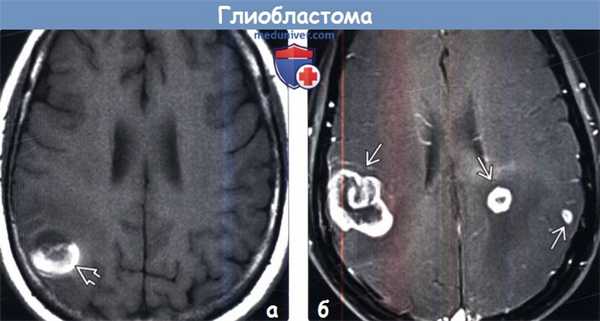

(а) МРТ, Т1-ВИ, аксиальный срез: у женщины 62 лет определяется объемное образование с геморрагическим компонентом (соответствующим областям укорочения Т1, что обусловлено наличием продуктов распада крови в подострой стадии). При биопсии была диагностирована МТБ. МТБ всегда нужно предполагать у пациентов старшего возраста с внутричерепным кровоизлиянием неясного генеза без артериальной гипертензии в анамнезе.

(б) МРТ, постконтрастное Т1-ВИ, аксиальный срез: у мужчины 72 лет визуализируются три отдельные зоны контрастирования, представляющие собой мультифокальную МГБ. Подобное синхронное возникновение МГБ встречается не более чем в 5% случаев.